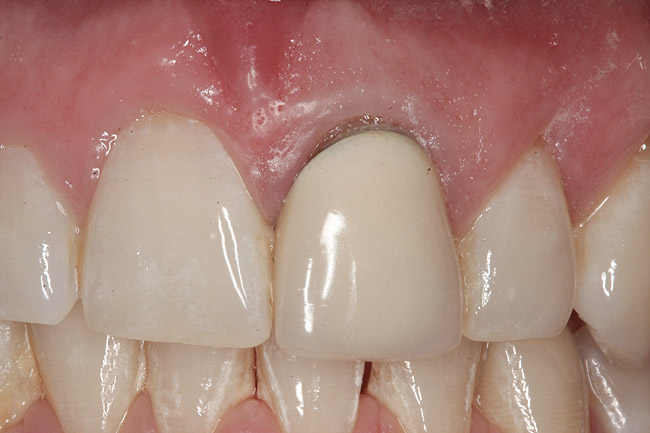

Fig 7. Blanching of the soft tissue.

Figure 7

The provisional is then trimmed of flash and polished, placed into the mouth, and hand tightened. Blanching of the soft tissue is seen as the result of the tissue slumping without the support of the tooth (Figure 7). The provisional is evaluated for proper free gingival margin positioning. The interdental papilla are assessed for volume and height, and the occlusion is checked. If there are any shortcomings, the provisional contours are adjusted. If the gingival margins are more apical than ideal, the cervical area of the provisional is relieved. If the free gingival margin is more coronal than the ideal position, the cervical area of the provisional is bulked out to move the soft tissue apically. Interdental papilla are altered by changing the contact point position, volume, and convexity of the proximal surfaces.10,11 Once the esthetic contours have been developed, a cotton pellet is placed over the screw head, the access hole is filled in with the material of choice, and the occlusion is checked. The goal is to achieve minimal centric contact with no contact in lateral excursions.